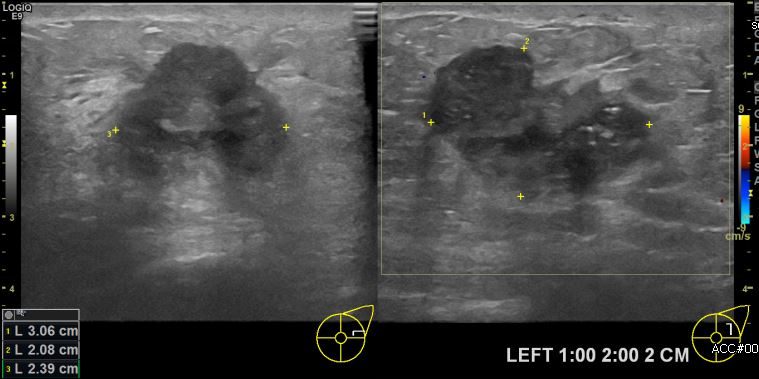

상기환자 좌측 유방에 멍울로 내원하신 50대 여성분으로 본원 초음파상 좌측 1시에서2시 방향에서 2cm 떨어진 거리에 만져지는 멍울 조직검사 시행하여 좌측 침윤성 유관암 진단 되었습니다.